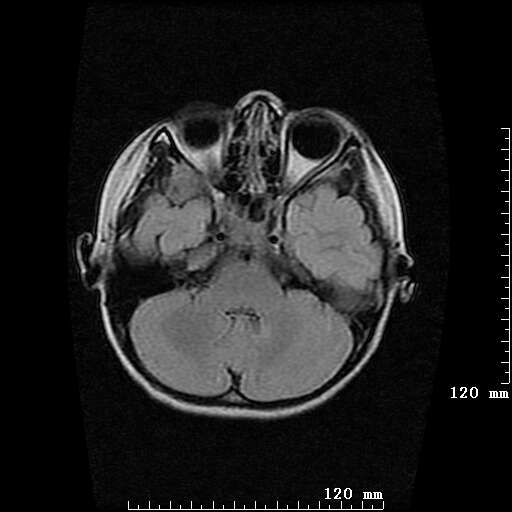

女,7岁,三岁才说话、走路。现智力尚可,走路不稳。临床怀疑大脑发育不全。

考虑 脑白质发育不良

脑折质变薄,双侧侧脑室稍扩张,支持考虑脑折质发育不良

侧脑室周围白质软化症。

考虑胼胝体发育不全,髓鞘形成不良。

支持考虑胼胝体发育不全,髓鞘形成不良。

脑裂畸形伴灰质异位

侧脑室周围白质数量减少,侧脑室不对称性扩大,左侧侧脑室后角呈方形改变,脑沟加深,结合临床考虑脑室周围白质软化症(pvl)。期待结果!

只看出灰质异位

支持脑白质发育不良。